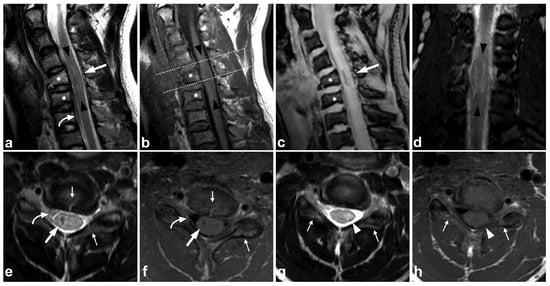

4.2. Posterior Ligament Complex

The posterior ligament complex (PLC) consists of the ligamentum flavum, interspinous ligament, supraspinous ligament, and facet joint capsules. It is noted as an essential factor for spinal stability in numerous classification systems proposed for spinal trauma [42]. Of these classifications, the TLICS [43,44,45] and AO Spine systems [43,46,47,48] have also been found to have good interrater reliability in the pediatric population. Dawkins et al. [44], however, concluded the interrater reliability of the TLICS classification to be lower with patients having undergone MRI than those treated based on CT imaging only. As the authors discussed, this is probably explained by MRI’s superior sensitivity in demonstrating stable PLC injuries that would be undetectable in CT or plain radiographs. It is possible that the MRI’s suggested poor interrater reliability with the TLICS classification could be improved with education, given that, in the study by Dawkins et al., spine surgeons with varying experience read the MRIs, and no radiologists were involved.

In addition to a widened interspinous distance and other indirect measures used with CT and plain radiographs, MRI can differentiate the very components of the PLC, revealing the culprits responsible for the indirect CT findings (Figure 9).

Figure 9.

(a) Sagittal STIR. (b) Sagittal T2-weighted. (c) Sagittal T1-weighted. (d,e) Axial T2-weighted, two adjacent slices at the level C6/7 (line on the image (c)). (f) Right-sided off-midline sagittal STIR. (g) Coronal STIR. (h) Left-sided off-midline sagittal STIR. A 9-year-old female, flexion injury in a trampoline accident. On level C2/3, there is slight edema in the posterior atlantoaxial membrane (PAAM), rectus capitis posterior major muscle, nuchal ligament, and adjacent deep cervical fat tissue (small white arrows). On level C6/7, we see more prominent edema of the interspinous and supraspinous ligaments (white arrows); there is a partial tear in the interspinous ligament. At this level, the ligamentum flavum is inhomogeneous (black arrowheads) due to a partial tear but without loss of continuity. A thin hematoma can also be seen between the flavum and posterior arch of C7 (white arrowheads, image (d)). Minor facet joint injury is also present; a small amount of fluid and edema can be seen at the left C2/3 facet joint and the posterior parts of both facet joints at level C6/7 (angled arrows). In addition to the PLC injury, there are compression fractures at the anterior parts of the vertebral bodies C7/Th3 (white asterisks). This is also a typical finding in flexion injuries of the cervical spine. The findings presented are highly unlikely to lead to instability, demanding a surgical fixation. However, this case demonstrates MRI’s power to directly assess the different stabilizing structures of the spine.